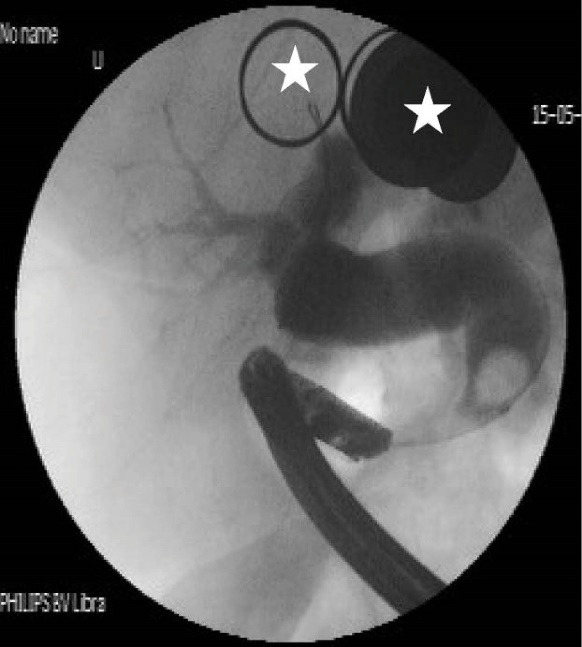

Table 2 shows detailed cholangiographic information about all patients. The indication of ERCP was recurrent acute cholangitis associated with bile duct dilatation in 20 patients and abdominal pain associated with elevated liver enzymes and dilatation of bile ducts in 9 patients. CBD cannulation was successful in all patients and we did not use needle knife papillotomy for cannulation in any patients. We could not pass the duodenoscope to the second portion of the duodenum because of apical stenosis in 5 patients; we used a gastroscope (because it is thinner than a duodenoscope) to visualize the second and third portion of the duodenum in those patients and confirmed that the opening site of CBD was located above the apical stenosis site. CBD cannulation and therapeutic intervention were performed with the duodenoscope in all patients. Cholangiography showed diffuse dilatation of the extrahepatic bile duct (median 17 mm: range 12 to 40 mm in diameter,) and intrahepatic bile ducts in all patients. The dilated CBD showed tapered narrowing and a hook-shaped distal end in all patients (Figure 4). Twenty-six out of 29 (89%) patients had bile stone (Figure 5) and three (10%) patients had sludge in bile ducts. We did not perform sphincterotomy in any patients because there was not enough incision distance. After cholangiography, we dilated the ectopic opening orifice with a pyloric dilatation balloon (range 12–18 mm in diameter) in all patients for stone and sludge extraction and for free biliary drainage. Complete stone extraction was achieved in 7 out of 26 (27%) patients with bile duct stone. In 19 patients whose stone could not be retrieved because of acute angulation, tapered narrowing and a hook-shaped distal end of CBD and un-effective pull back of balloon catheter for extraction of stones, a nasobiliary drain (n = 12 patients) or stent (n = 7) was placed for prevention of cholangitis. We did not observe any complications such as bleeding, perforation and acute pancreatitis related to ERCP and balloon dilatation. The pancreatic ducts were opacified in 5 out of 29(17%) patients via separate opening site and there was not any communication between the pancreatic canal and bile ducts. We did not opacify the pancreatic canal in the remaining 24 patients because our primary aim was to perform biliary therapeutic intervention.

Patients with ectopic opening of the CBD usually have clinical symptoms and signs of biliary tract diseases. Dilatation of intrahepatic and extrahepatic bile ducts, a hook-shaped configuration of the distal end of the CBD and biliary stones were the most common ERCP findings in this anomaly. The most common clinical presentations in these patients are bile duct stones, recurrent cholangitis, obstructive jaundice and abnormal liver function tests.1–6 Normal sphincteric musculature is absent around the entrance of accessory bile ducts into the gastrointestinal tract.14,18 In our case series, we found diffuse dilatation in both extrahepatic and intrahepatic bile ducts in all patients. We did not identify any stricture preventing biliary drainage on cholangiography in any patients. Because of the presence of diffuse dilatation in bile ducts, we can speculate that in addition to acute angulation of the distal end of the CBD, sphincter dysfunction may impede normal bile stream and cause chronic bile stasis, bile duct dilatation and formation of biliary sludge and bile stone. Manometric measurement may yield more accurate information about sphincter functions in these patients.

In patients with ectopic opening of CBD together with bile duct stones, it is usually difficult to remove the stones by ERCP. Normal sphincteric structure is absent around the opening site. Therefore, there is a high risk of perforation and bleeding during endoscopic sphincterotomy. For this reason, endoscopic sphincterotomy should be avoided in these patients. Endoscopic balloon dilatation may be an alternative to sphincterotomy in these patients.1,11,12,15 We showed that balloon dilatation is an effective and reliable intervention in patients with this abnormality. However, acute angulation, tapered narrowing and a hook-shaped distal end of CBD and deformity of the duodenal bulb usually prevent effective pull back of balloon catheter for extraction of stones. Therefore, we did not achieve complete stone extraction in most of our patients. Because most of the patients with this abnormality have recurrent cholangitis, large bile stones and apical stenosis, surgery may be an effective alternative treatment modality for patients whose stone could not be retrieved by endoscopic intervention.